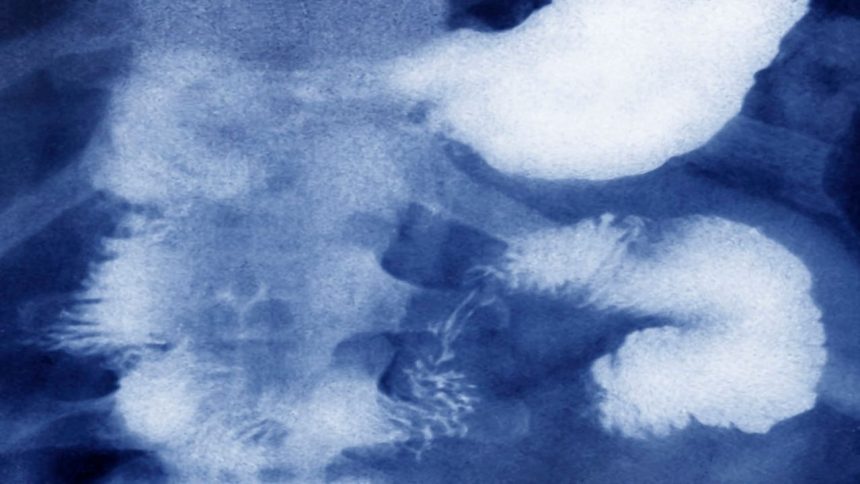

After this, the boy started complaining of abdominal pain. On October 26, an extensive ultrasound test in Aligarh detected that there were as many as 19 objects lodged inside his stomach. The family took him to a private hospital in Noida immediately. Sharma said that in Noida, doctors found 42 objects in the stomach of Aditya and they said it needed urgent medical attention. The boy was then taken to Delhi’s Safdarjung Hospital, where a scan found as many as 65 objects, and Aditya’s “heart beat raced up to 280 per minute”, according to the family. Hours after the gruelling surgery, the boy breathed his last.